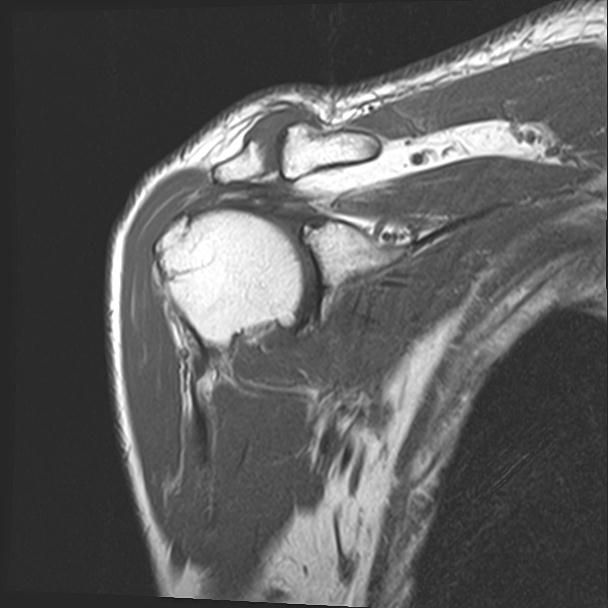

60058 3/9 11/4 右肩 2R+MRI 73歳男性 肩腱板損傷